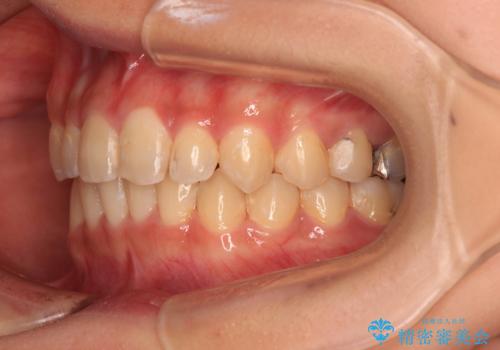

深い咬み合わせとデコボコの歯列をワイヤー矯正で改善

- 前歯のデコボコと深い咬み合わせを改善したいとのことで来院された患者様です。

奥歯の咬み合わせは上顎に対して下顎が後方位にあり、上顎前歯で下顎前歯が隠れるような典型的な過蓋咬合です。